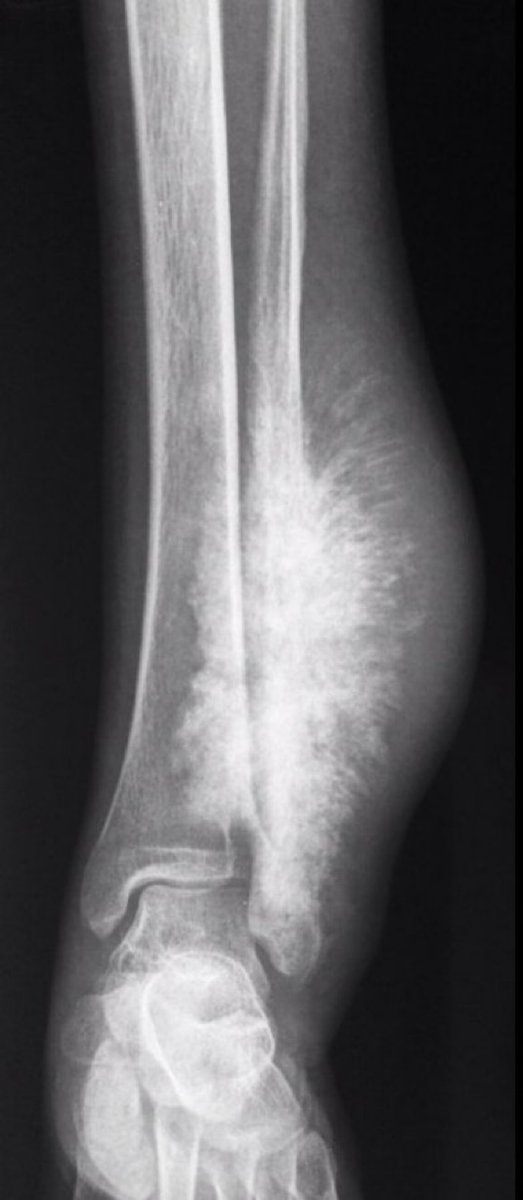

Image Radiopaedia

Representative X ray Appearance Of A Primary Benign Bone Tumor

Sunburst Appearance Pacs

Osteogenic Sarcoma Sunburst